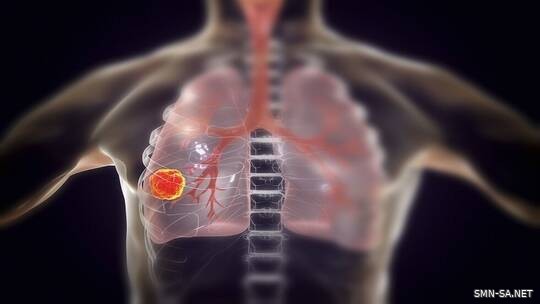

مادة غذائية يؤدي استهلاكها اليومي إلى الحد من خطر سرطان الرئة

الشبكة الإعلامية السعودية _ دعاء الحربي وجدت دراسة جديدة ، أجراها المركز الطبي في جامعة Vanderbilt بولاية تينيسي الأمريكية ، أن تناول كوب من اللبن (الزبادي) يوميا قد يقلل من خطر الإصابة بسرطان الرئة .

وتمكّن الأفراد الذين يتناولون اللبن يوميا ، إلى جانب اتباع نظام غذائي غني بالألياف ، من خفض خطر الإصابة بسرطان الرئة بأكثر من 30% .

وأظهرت الدراسات أن بعض أنواع البكتيريا الحية الموجودة في اللبن (بروبيوتيك) لها خصائص مضادة للالتهابات ومقاومة للسرطان .